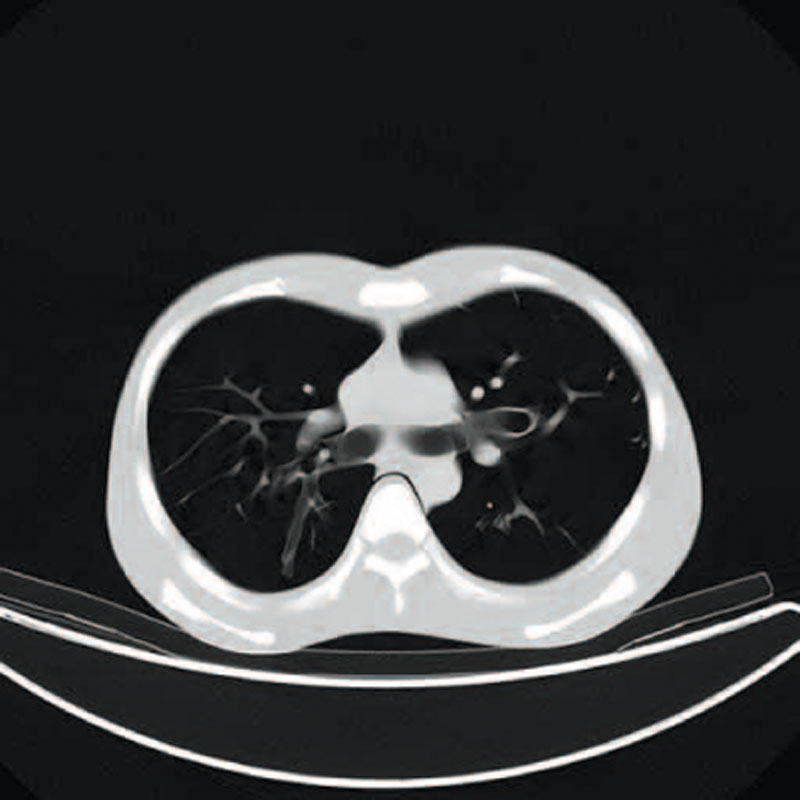

Ein einzigartiges Ganzkörperphantom für CT bietet eine Vielzahl von Ausbildungs- und Forschungsmöglichkeiten. Das Phantom kann auch für normales Röntgen benutzt werden und gibt lebensnahe Bilder. Es benden sich keine Metallteile oder Flüssigkeiten im Phantom. Die wichtigen Gelenke haben eine menschenähnliche Beweglichkeit und erlauben vielfältige Positionen für die Übung. Das Phantom kann in 10 Teile zerlegt werden. Die verbesserten Schultergelenke erlauben es, die Arme nach oben zu bewegen. Die künstlichen Organe sind anatomisch korrekt und haben entsprechende HU-Zahlen.

- Lungen mit Pulmonalgefäßen

- Luftröhre

Radiologische Absorption und Hounsfield-Nummer ähnlich dem menschlichen Körper.